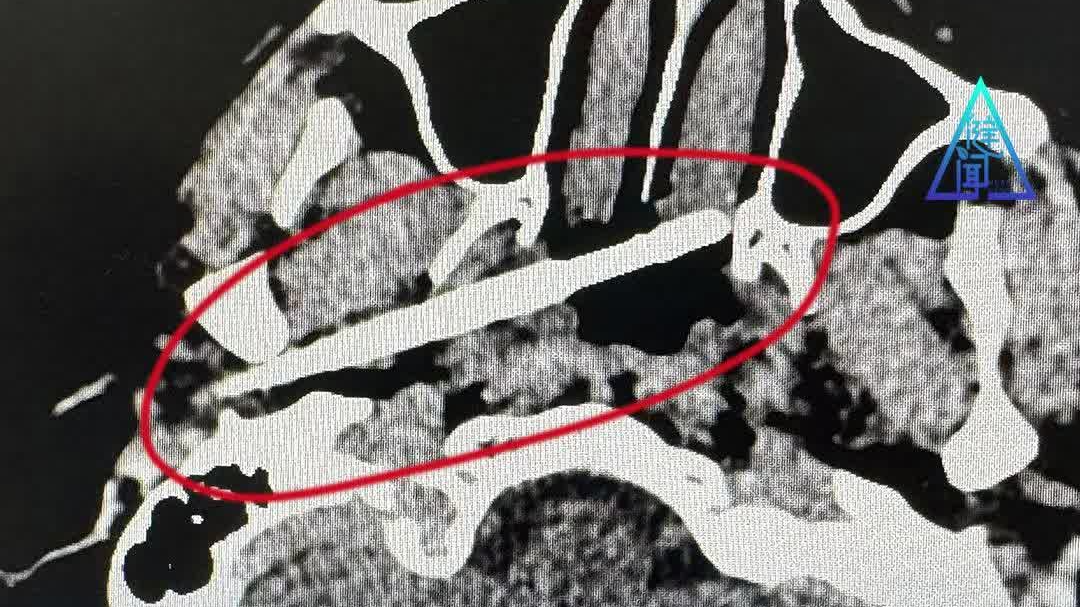

男子与人争执受伤,筷子从耳部插入颅底,距大动脉仅5毫米!